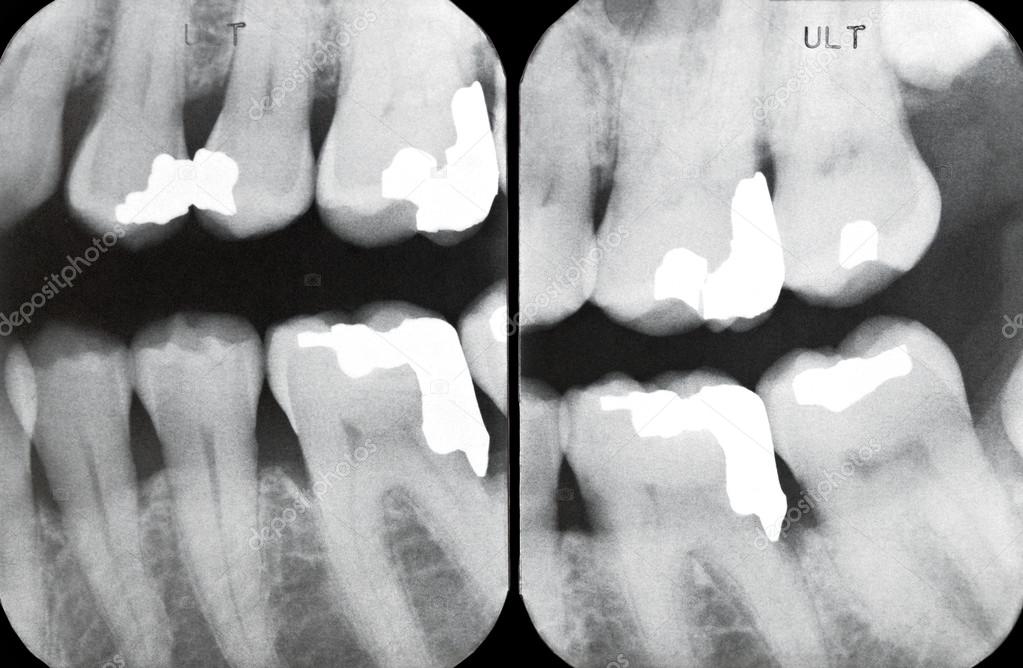

From depositphotos.com

Right Periodontal X rays Stock Photo by ©Lawcain 67906335 Can You See Periodontal Disease On An X Ray a range of findings of relevance to clinically evident periodontal conditions can become apparent on radiographs. Your dental professional may also refer you to a. Can You See Periodontal Disease On An X Ray.